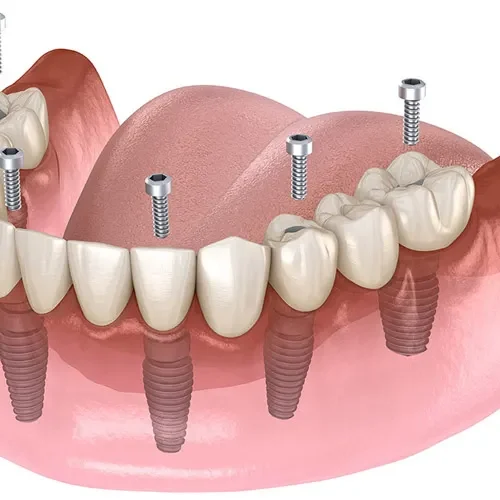

All on Four ve All on Six İmplant

Tamamen dişsiz veya kalan dişleri çekilmesi gereken hastalar için tek bir operasyonda ve tek bir protez ile sabit dişlere kavuşma imkanı sunan yenilikçi çözümlerdir. Hızlı iyileşme ve yüksek konfor sunar.

3) All-on-Four / All-on-Six bana uygun mu?

Tam dişsizlikte tek aşamada sabit proteze geçiş için iyi seçeneklerdir. Kemik hacmi, sistemik durum, sigara alışkanlığı ve hijyen motivasyonu değerlendirilir. Geçici–kalıcı protez zamanlaması hastaya özelleştirilir.